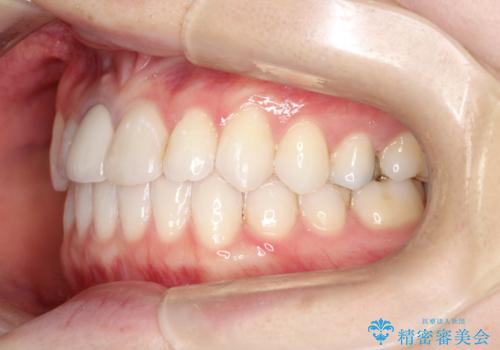

- 前歯の凸凹を主訴に来院されました。

インビザラインにて短期間で満足いく結果が得られたと大変喜ばれました。

歯と歯の間に僅かなスペースを作って配列していました。追加アライナーを1回行っています。